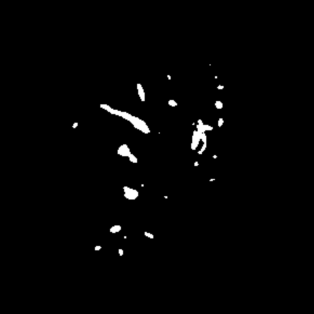

Manually segmenting the hepatic vessels from Computer Tomography (CT) is far more expertise-demanding and laborious than other structures due to the low-contrast and complex morphology of vessels, resulting in the extreme lack of high-quality labeled data. Without sufficient high-quality annotations, the usual data-driven learning-based approaches struggle with deficient training. On the other hand, directly introducing additional data with low-quality annotations may confuse the network, leading to undesirable performance degradation. To address this issue, we propose a novel mean-teacher-assisted confident learning framework to robustly exploit the noisy labeled data for the challenging hepatic vessel segmentation task. Specifically, with the adapted confident learning assisted by a third party, i.e., the weight-averaged teacher model, the noisy labels in the additional low-quality dataset can be transformed from "encumbrance" to "treasure" via progressive pixel-wise soft-correction, thus providing productive guidance. Extensive experiments using two public datasets demonstrate the superiority of the proposed framework as well as the effectiveness of each component.